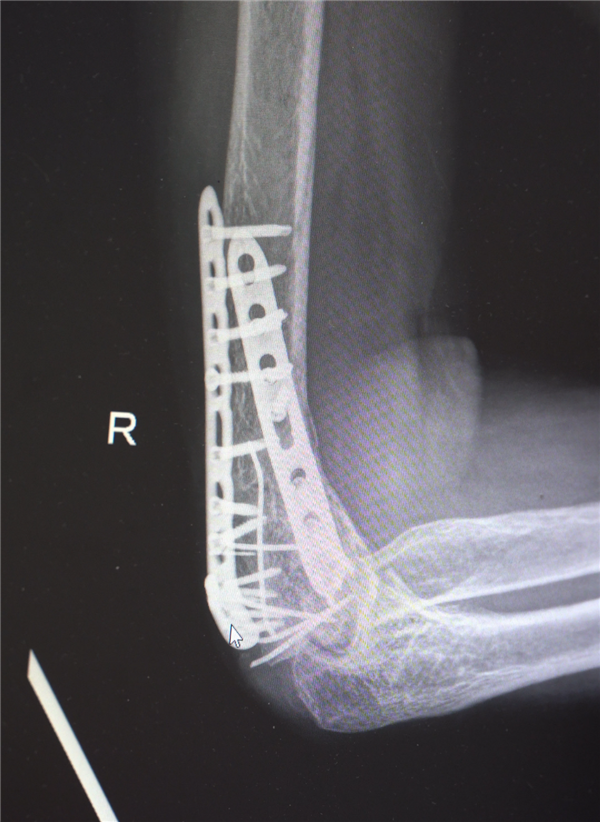

鉴于男子多处骨折,其中最严重的当属右肘部C3型粉碎性骨折,关节面及髁上严重粉碎(碎成了七块),肘关节易粘连,复位固定难度极高。

最终医疗团队采用了“拼古董”式复位固定技术,就像修复一件珍贵的古董瓷器,先拼接大块骨块再贴合小块,先后进行了两次手术。